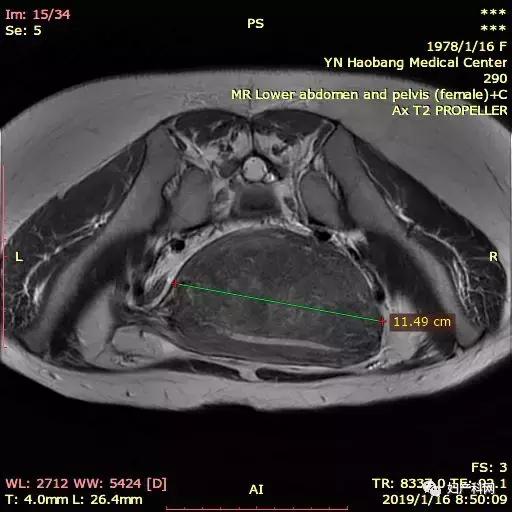

MRI如下:

因为这个患者子宫比较大,同时还有比较重的贫血貌,所以就诊时查了一下血常规仅有60+g/L,这样的情况下直接治疗不仅难度大,术后恢复也相对比较慢。所以我们先给予了患者一只10.8mg的诺雷德,希望她能够这几个月不来月经,避免进一步的丢失,同时开始口服铁剂补血,从1月底患者就诊到4月安排治疗,3个月的时间血色素恢复到了102g/L,子宫腺肌症的范围也从1月的12×7×11cm缩小到了8×5×7.5cm,治疗当天我们使用经皮的微波治疗,功率50w治疗6min10s,60w治疗9min36s,进行超声造影消融满意,于宫腔内放置了曼月乐环1枚。